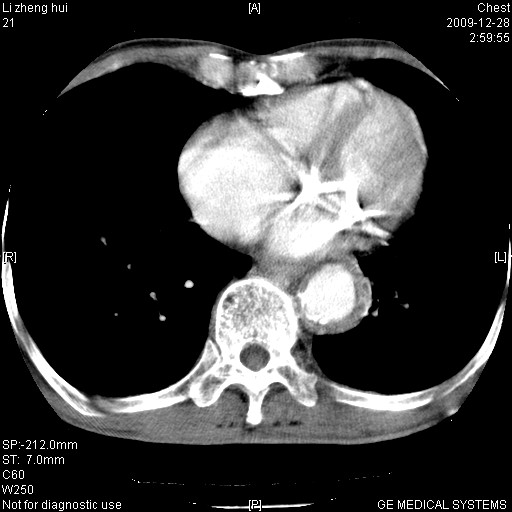

标题: CT23859:胸主动脉瘤 [打印本页]

标题: CT23859:胸主动脉瘤

男  79岁 胸部痛急诊入院,晚上做的增强

考虑主动脉瘤?(增粗、钙化、壁血栓?)

动脉瘤伴附壁血栓

1)考虑胸主动脉壁间血肿或夹层动脉瘤。2)多发性肝囊肿。

1)考虑胸主动脉附壁血栓或夹层动脉瘤。2)多发性肝囊肿。